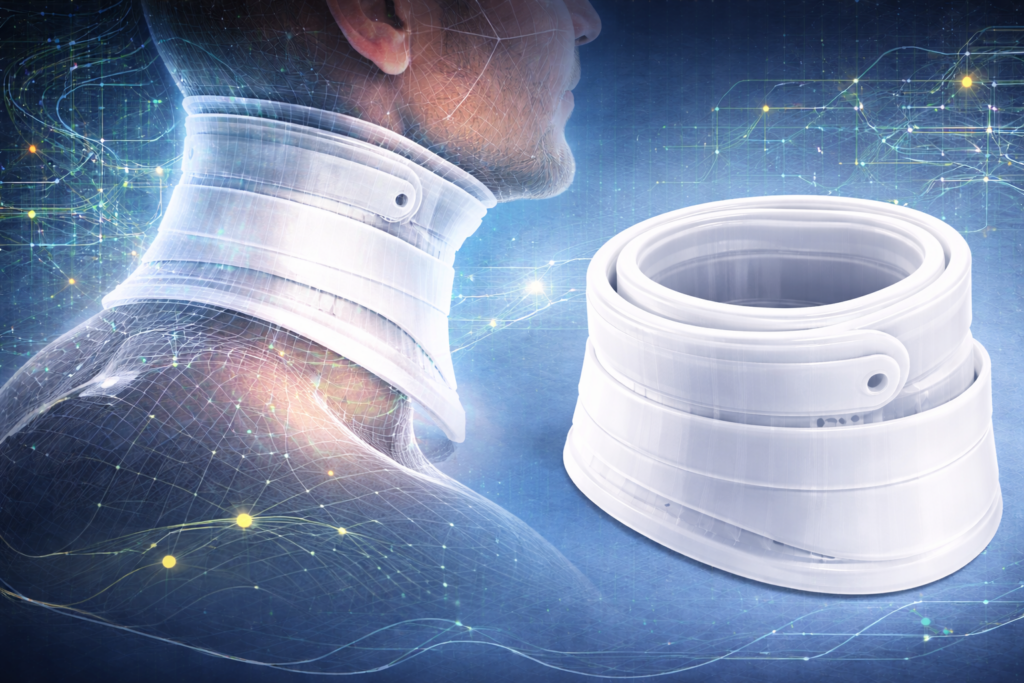

Oblast istraživanja Ergonomska i funkcionalna optimizacija pomagala za imobilizaciju vratne kičme sa fokusom na personalizaciju putem digitalnih tehnologija i samostalnu upotrebu. Tema istraživanja Dizajn i razvoj personalizovane modularne vratne kragne zasnovane na digitalnom modelovanju i unapređenim ergonomskim karakteristikama. Stanje u...

U trećoj fazi istraživanja fokus je bio na primeni prethodno ispitanih metoda na razvoj personalizovane vratne ortoze. Cilj ove faze bio je formiranje ortoze koja prati anatomiju vrata, omogućava lakše postavljanje na telo i može fizički da se realizuje korišćenjem...

U drugoj fazi istraživanja fokus je bio na proveri metoda parametarskog modelovanja i razvijanja površi kroz jednostavniji primer modela ruke, pre njihove primene na složenijoj formi vratne ortoze. Kao osnova korišćen je postojeći 3D model ruke, koji je skaliran prema...